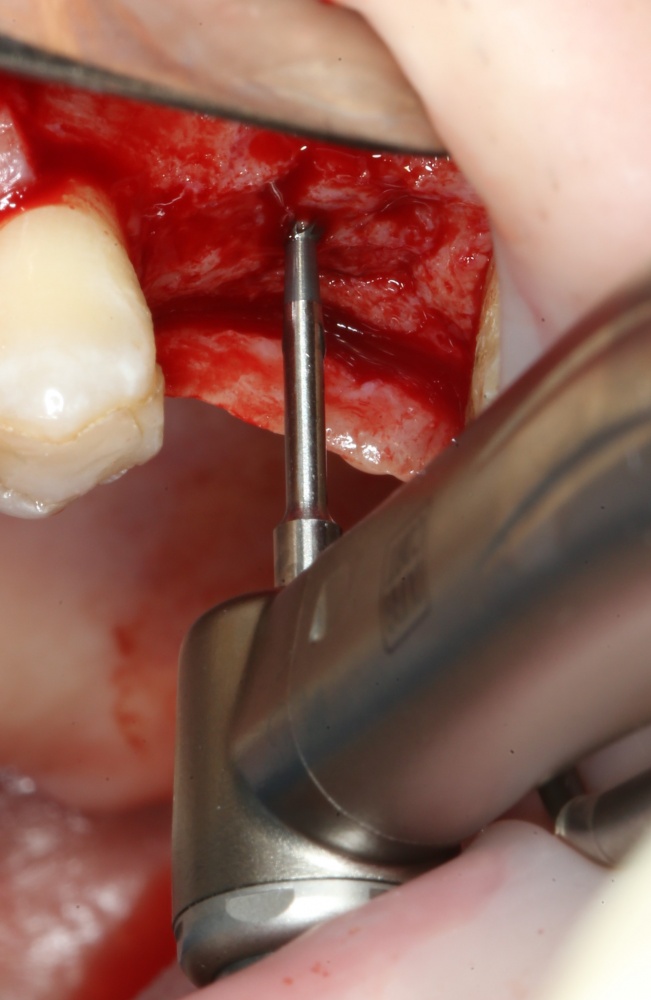

Первым инструментом из хирургического набора является шариковый бор. Он нужен для того, чтобы разметить положение имплантата:

Многие доктора (и некоторые производители имплантационных систем) заменяют шариковый бор в хирургическом наборе на фрезу Линдеманна или пику. На самом деле, шарик намного удобнее, поскольку не заклинивает в плотной кости, может работать любой поверхностью, а его основная функция — поставить точку на поверхности альвеолярного гребня, через которую потом пройдёт ось имплантата. Так что совсем уж углубляться шариком в кость не нужно. Тем более, не стоит проходить им всю глубину будущей лунки. Поставили точку — и всё на этом.

После этого можно еще раз (последний, кстати), проверить направление и ангуляцию оси будущего имплантата. Всё тем же вышеозначенным пином: